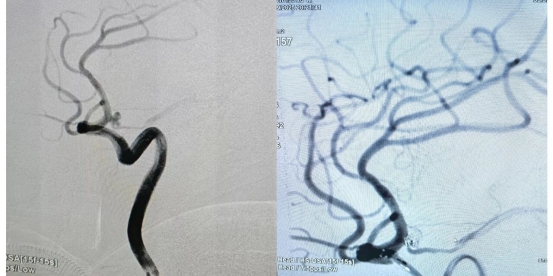

术中,熊海兵主治医师与我院神经外科团队紧密配合,凭借精湛的技术,成功通过微导管将栓塞材料精准填入动脉瘤腔内。术后造影显示,动脉瘤被完全致密填塞,不再显影,载瘤血管通畅无碍。手术取得圆满成功,患者顺利返回病房。

术前(左侧图像):动脉瘤引起出血,血管痉挛。

术后(右侧图像):脑血管恢复正常的形态,血管网络通畅。